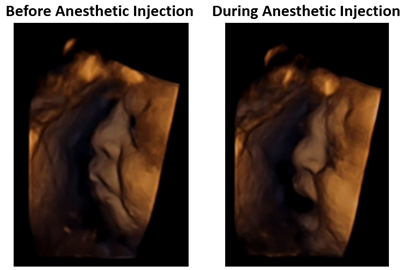

Advancements in prenatal imaging and surgical technology, combined with discoveries in anesthesia for relieving pain, were pivotal in ushering in the modern era of fetal surgery. Today, unborn babies are routinely treated inside the womb, receiving anesthesia and other pain relief like any other patient, from as early as 15 weeks. Review the science here and here.

Watch 4D ultrasound video of a baby (third trimester) reacting to an injection of anesthetic prior to surgery in utero HERE.